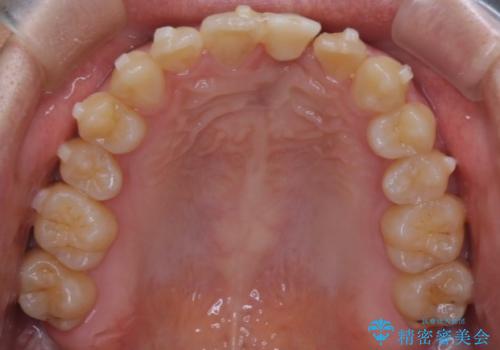

前歯の開咬とシザーズバイトを改善|インビザライン矯正

- 前歯が噛み合わない(開咬)ことと、奥歯の噛み合わせが交叉している(シザーズバイト)ことを改善するため、インビザラインによるマウスピース矯正を計画しました。精密な口腔内スキャナーを用いたシミュレーションで歯の移動経路を確認し、効果的な治療計画を立案。奥歯の咬合関係を整え、前歯の咬合を確立することを目指し、約1年半〜2年で治療を完了する予定としました。

前歯が噛まないため咀嚼が困難で、シザーズバイトにより噛み合わせに不調を感じていました。インビザラインを用いて、透明なマウスピースによる目立ちにくい矯正治療を実施。奥歯のシザーズバイトを改善した後、前歯の歯列を緻密に調整し、噛み合わせを整えました。定期的なマウスピース交換を通じて徐々に歯列が改善され、治療終了後には前歯が正常に咬合するようになり、噛み合わせの機能性と審美性が共に向上しました。